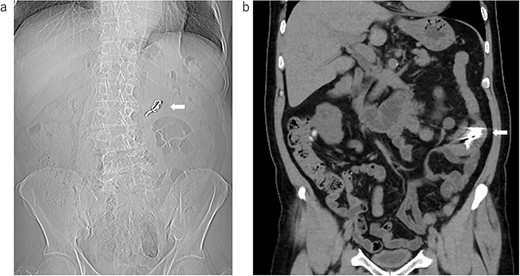

Abdominal examination findings were normal. Blood exams showed no unusual findings except slight renal dysfunction (BUN 38.2 mg/dl, Cre 1.98 mg/dl). We asked the previous doctor to provide the results of the imaging test (Fig. 1a and b). After that, we performed X-ray (Fig. 2a) and CT (Fig. 2b) examinations at our hospital and confirmed that the denture was still in the small intestine. Since it remained in the intestinal tract for a long time, there was no possibility of spontaneous excretion. Although the patient was asymptomatic, we decided to perform surgery because the patient himself wanted to have it removed.

The image data were obtained at our hospital; (a) X-ray examination: the arrow shows the swallowed denture; (b) the coronal image of the CT: the arrow shows the swallowed denture.